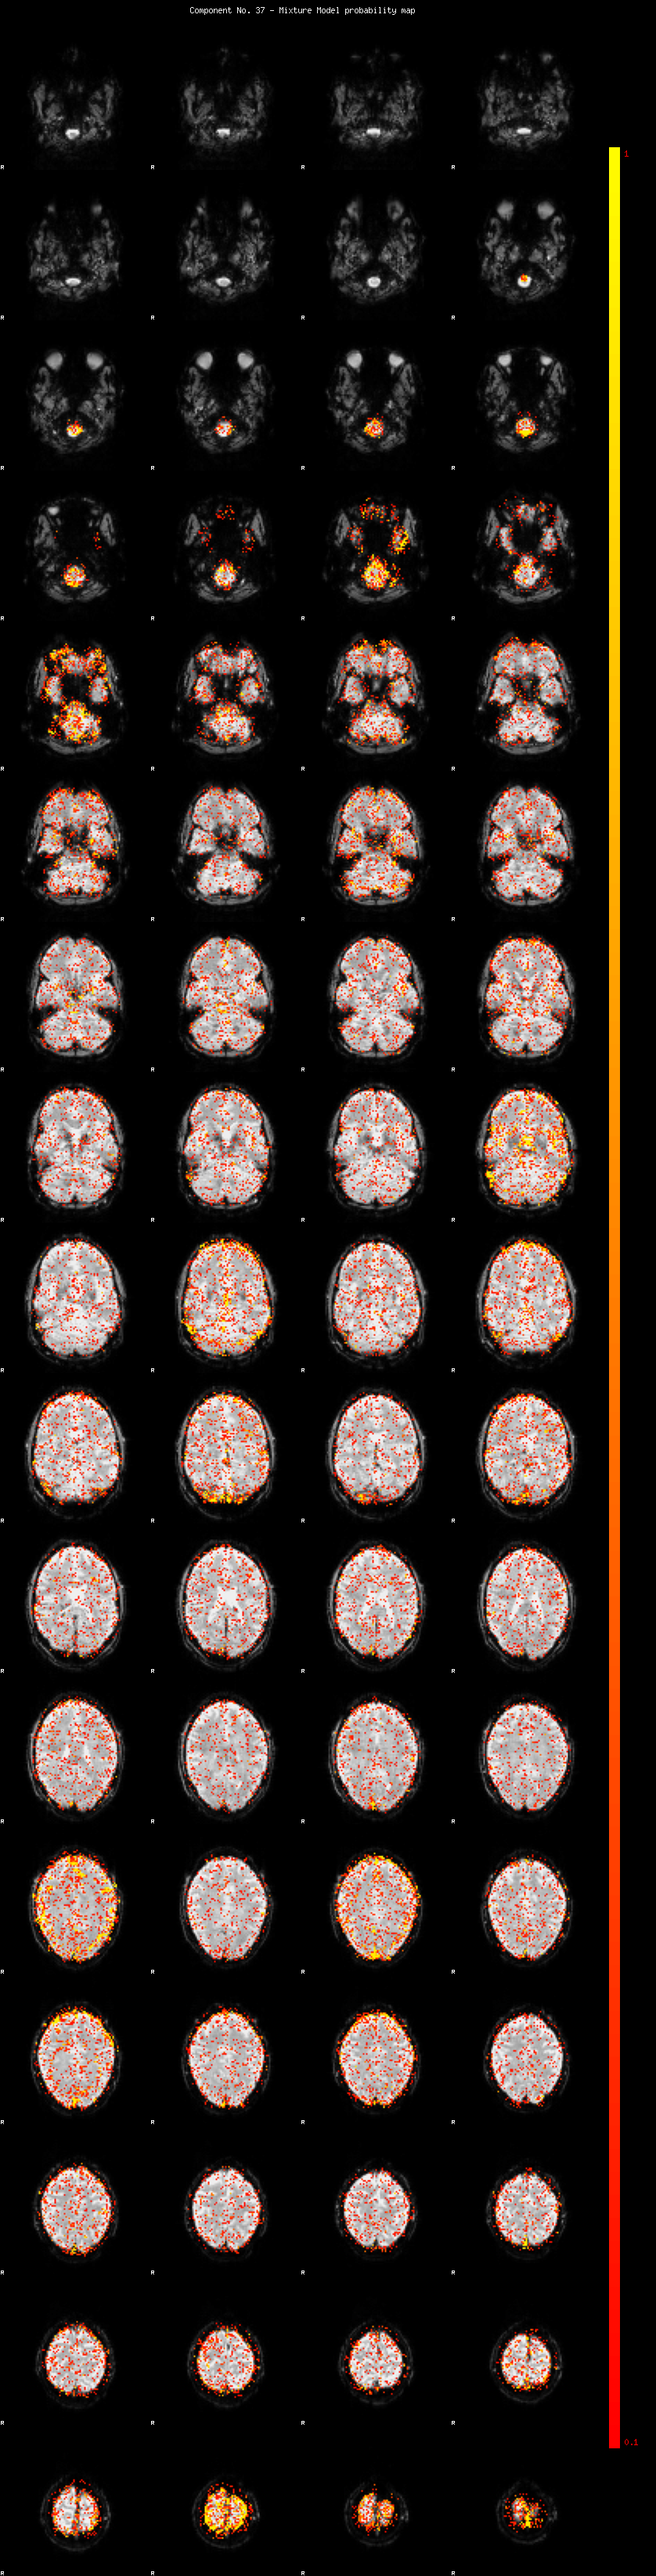

IC_37 Mixture Model fit

Means : -0.000000 2.451697 -2.267468

Vars : 1.000000 1.878576 1.354735

Prop. : 0.923431 0.042560 0.034008